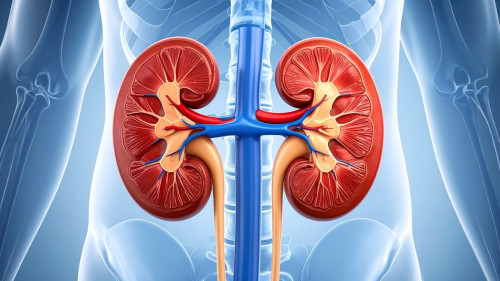

Kidney failure occurs when the kidneys can no longer perform their functions effectively, such as filtering metabolic waste, maintaining fluid balance, and regulating electrolytes in the body.

The kidneys play an important role in maintaining overall body balance by:

- Filtering metabolic waste from the blood

- Regulating fluid and electrolyte balance

- Controlling blood pressure

- Producing erythropoietin hormone to support red blood cell production [2.1]